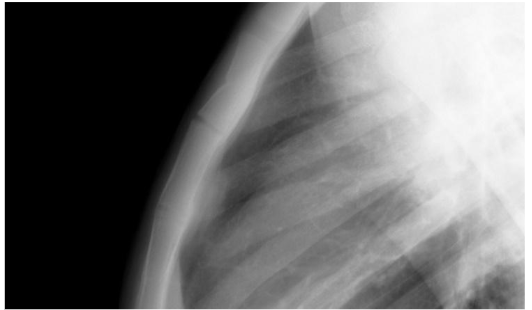

Rib Fractures

Posterior rib fractures are especially specific for nonaccidental trauma and may not have any overlying skin changes such as ecchymosis. They may result from a child’s torso being squeezed inappropriately by a caregiver.